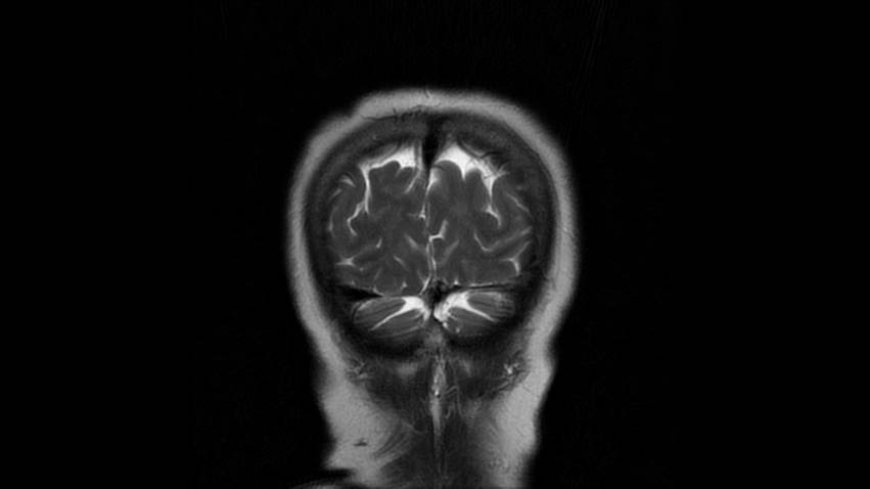

MRI of Brain

Coronal T2